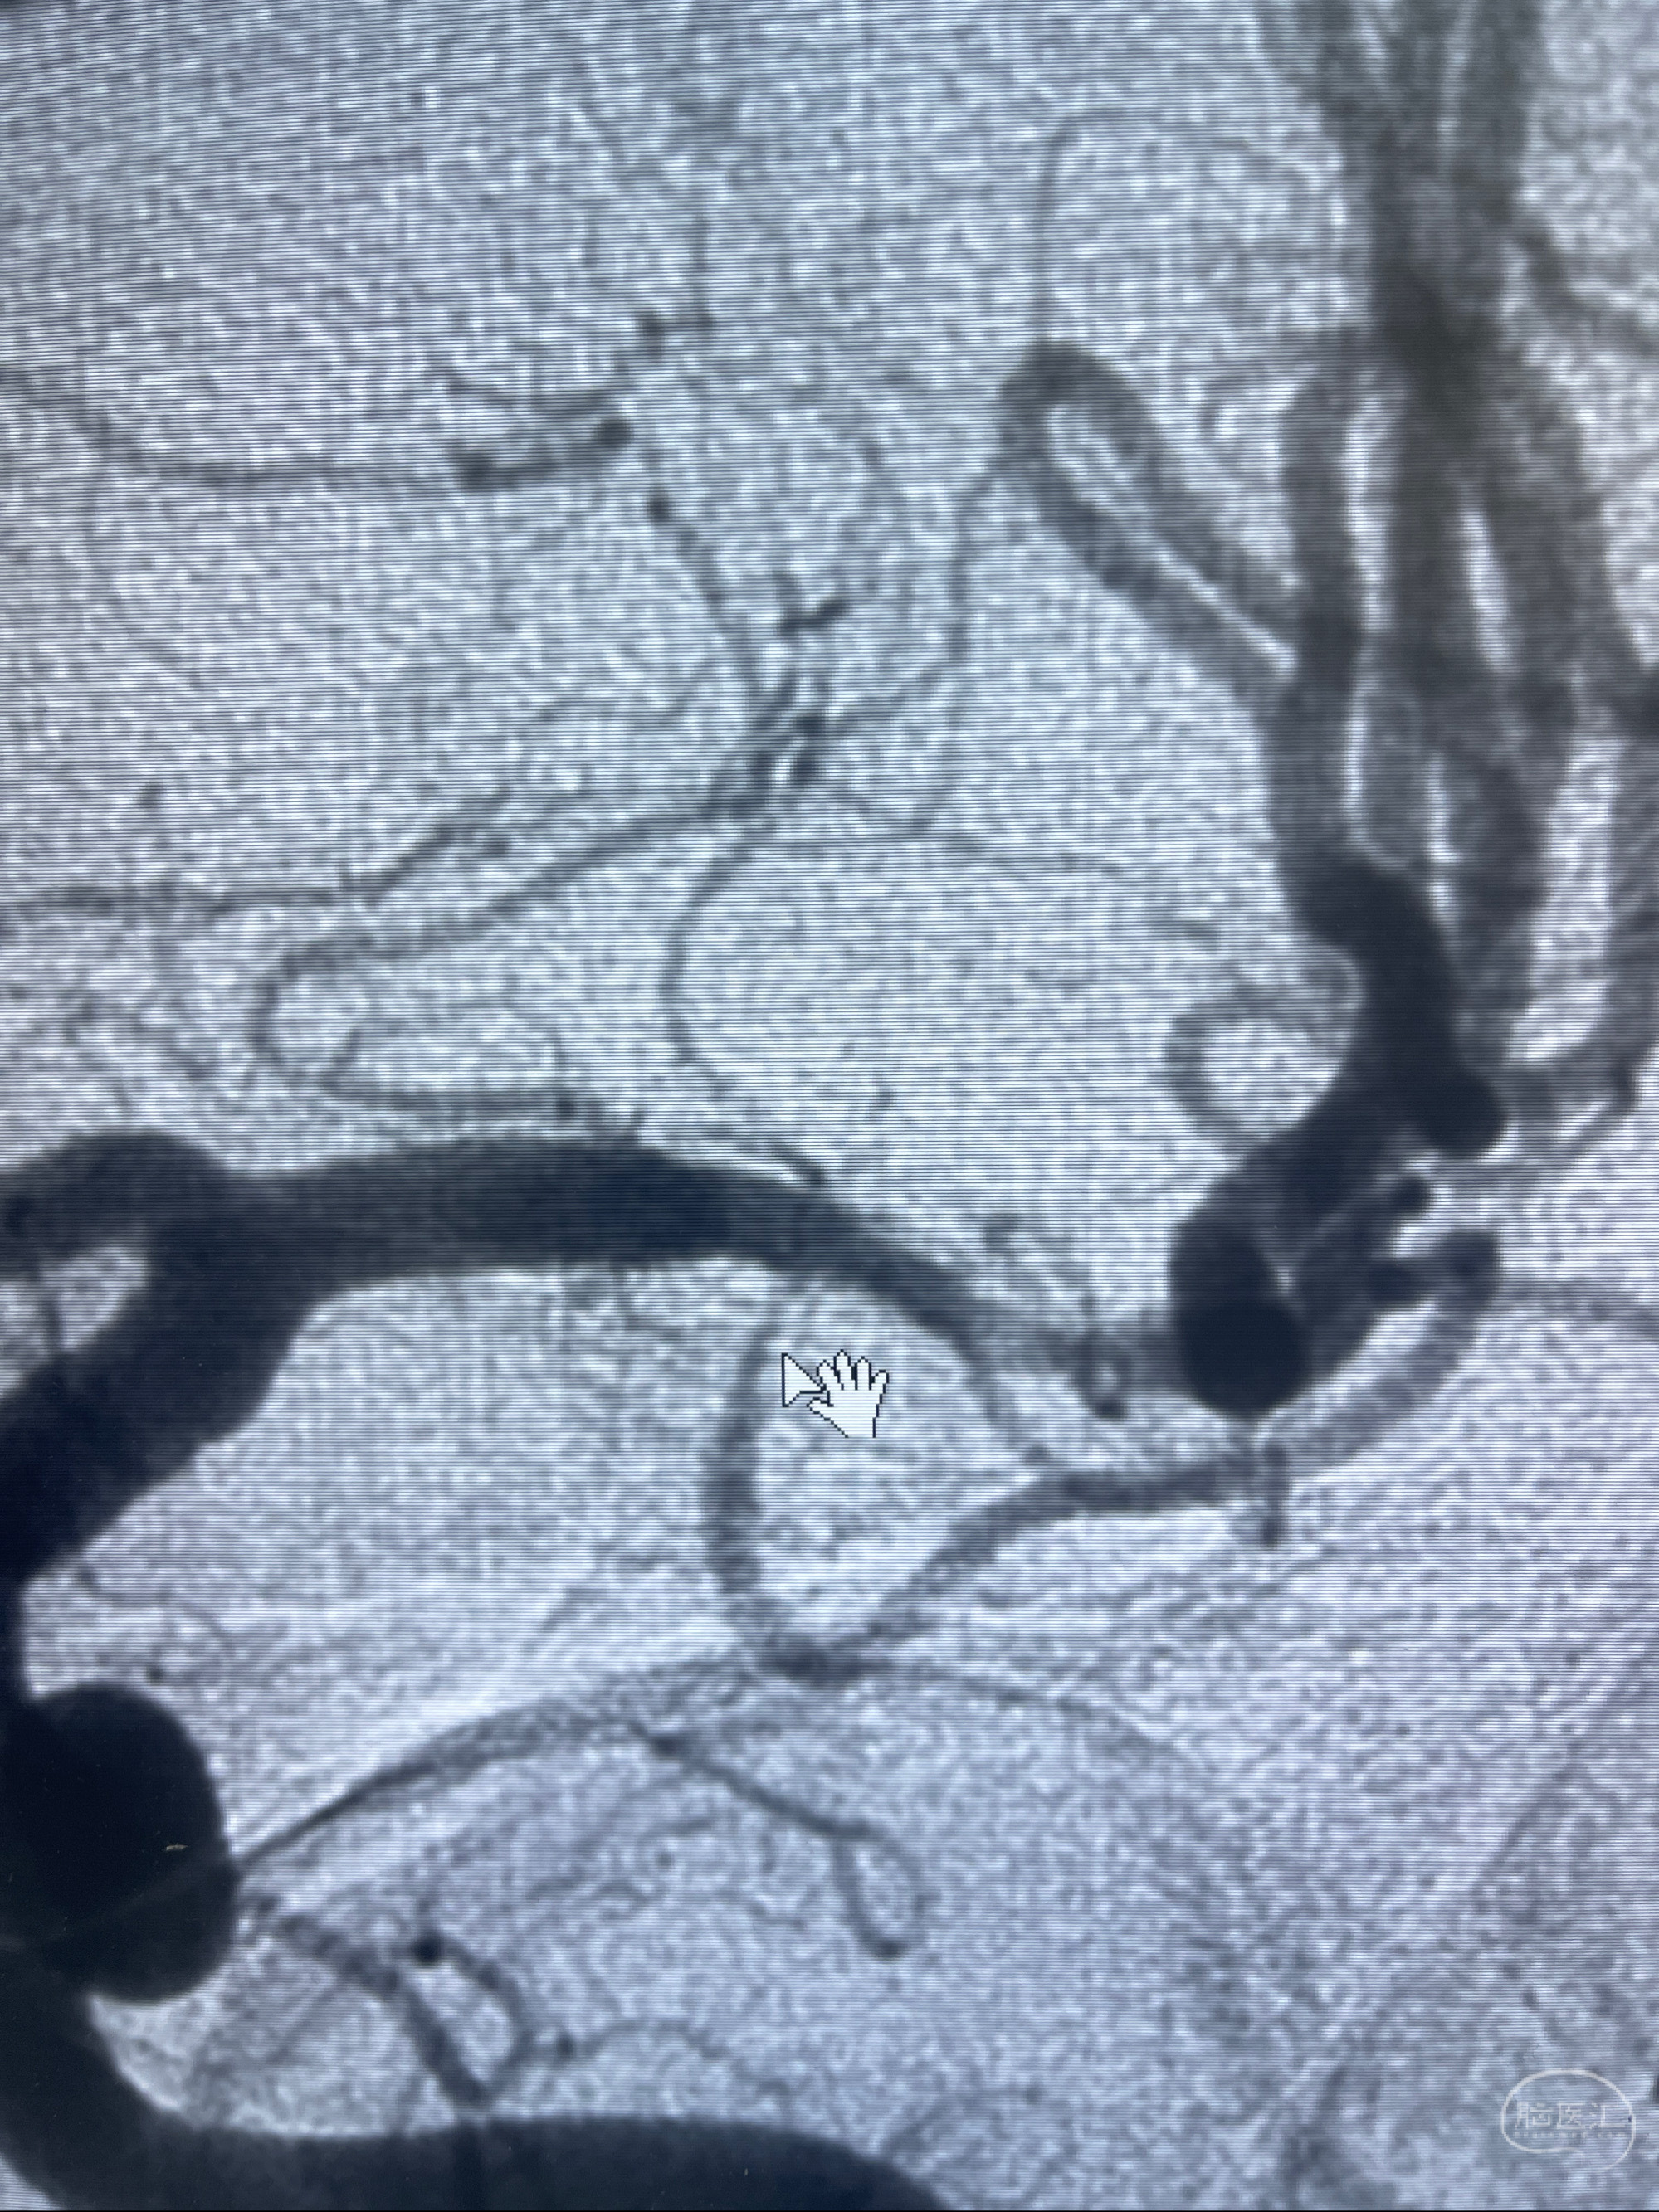

2023-02-02 沛县人民医院 头颅CTA:大脑动脉环发育变异,头颈部动脉粥样硬化,双侧颈内动脉及椎动脉颅内段多发狭窄;

2023-02-15DSA